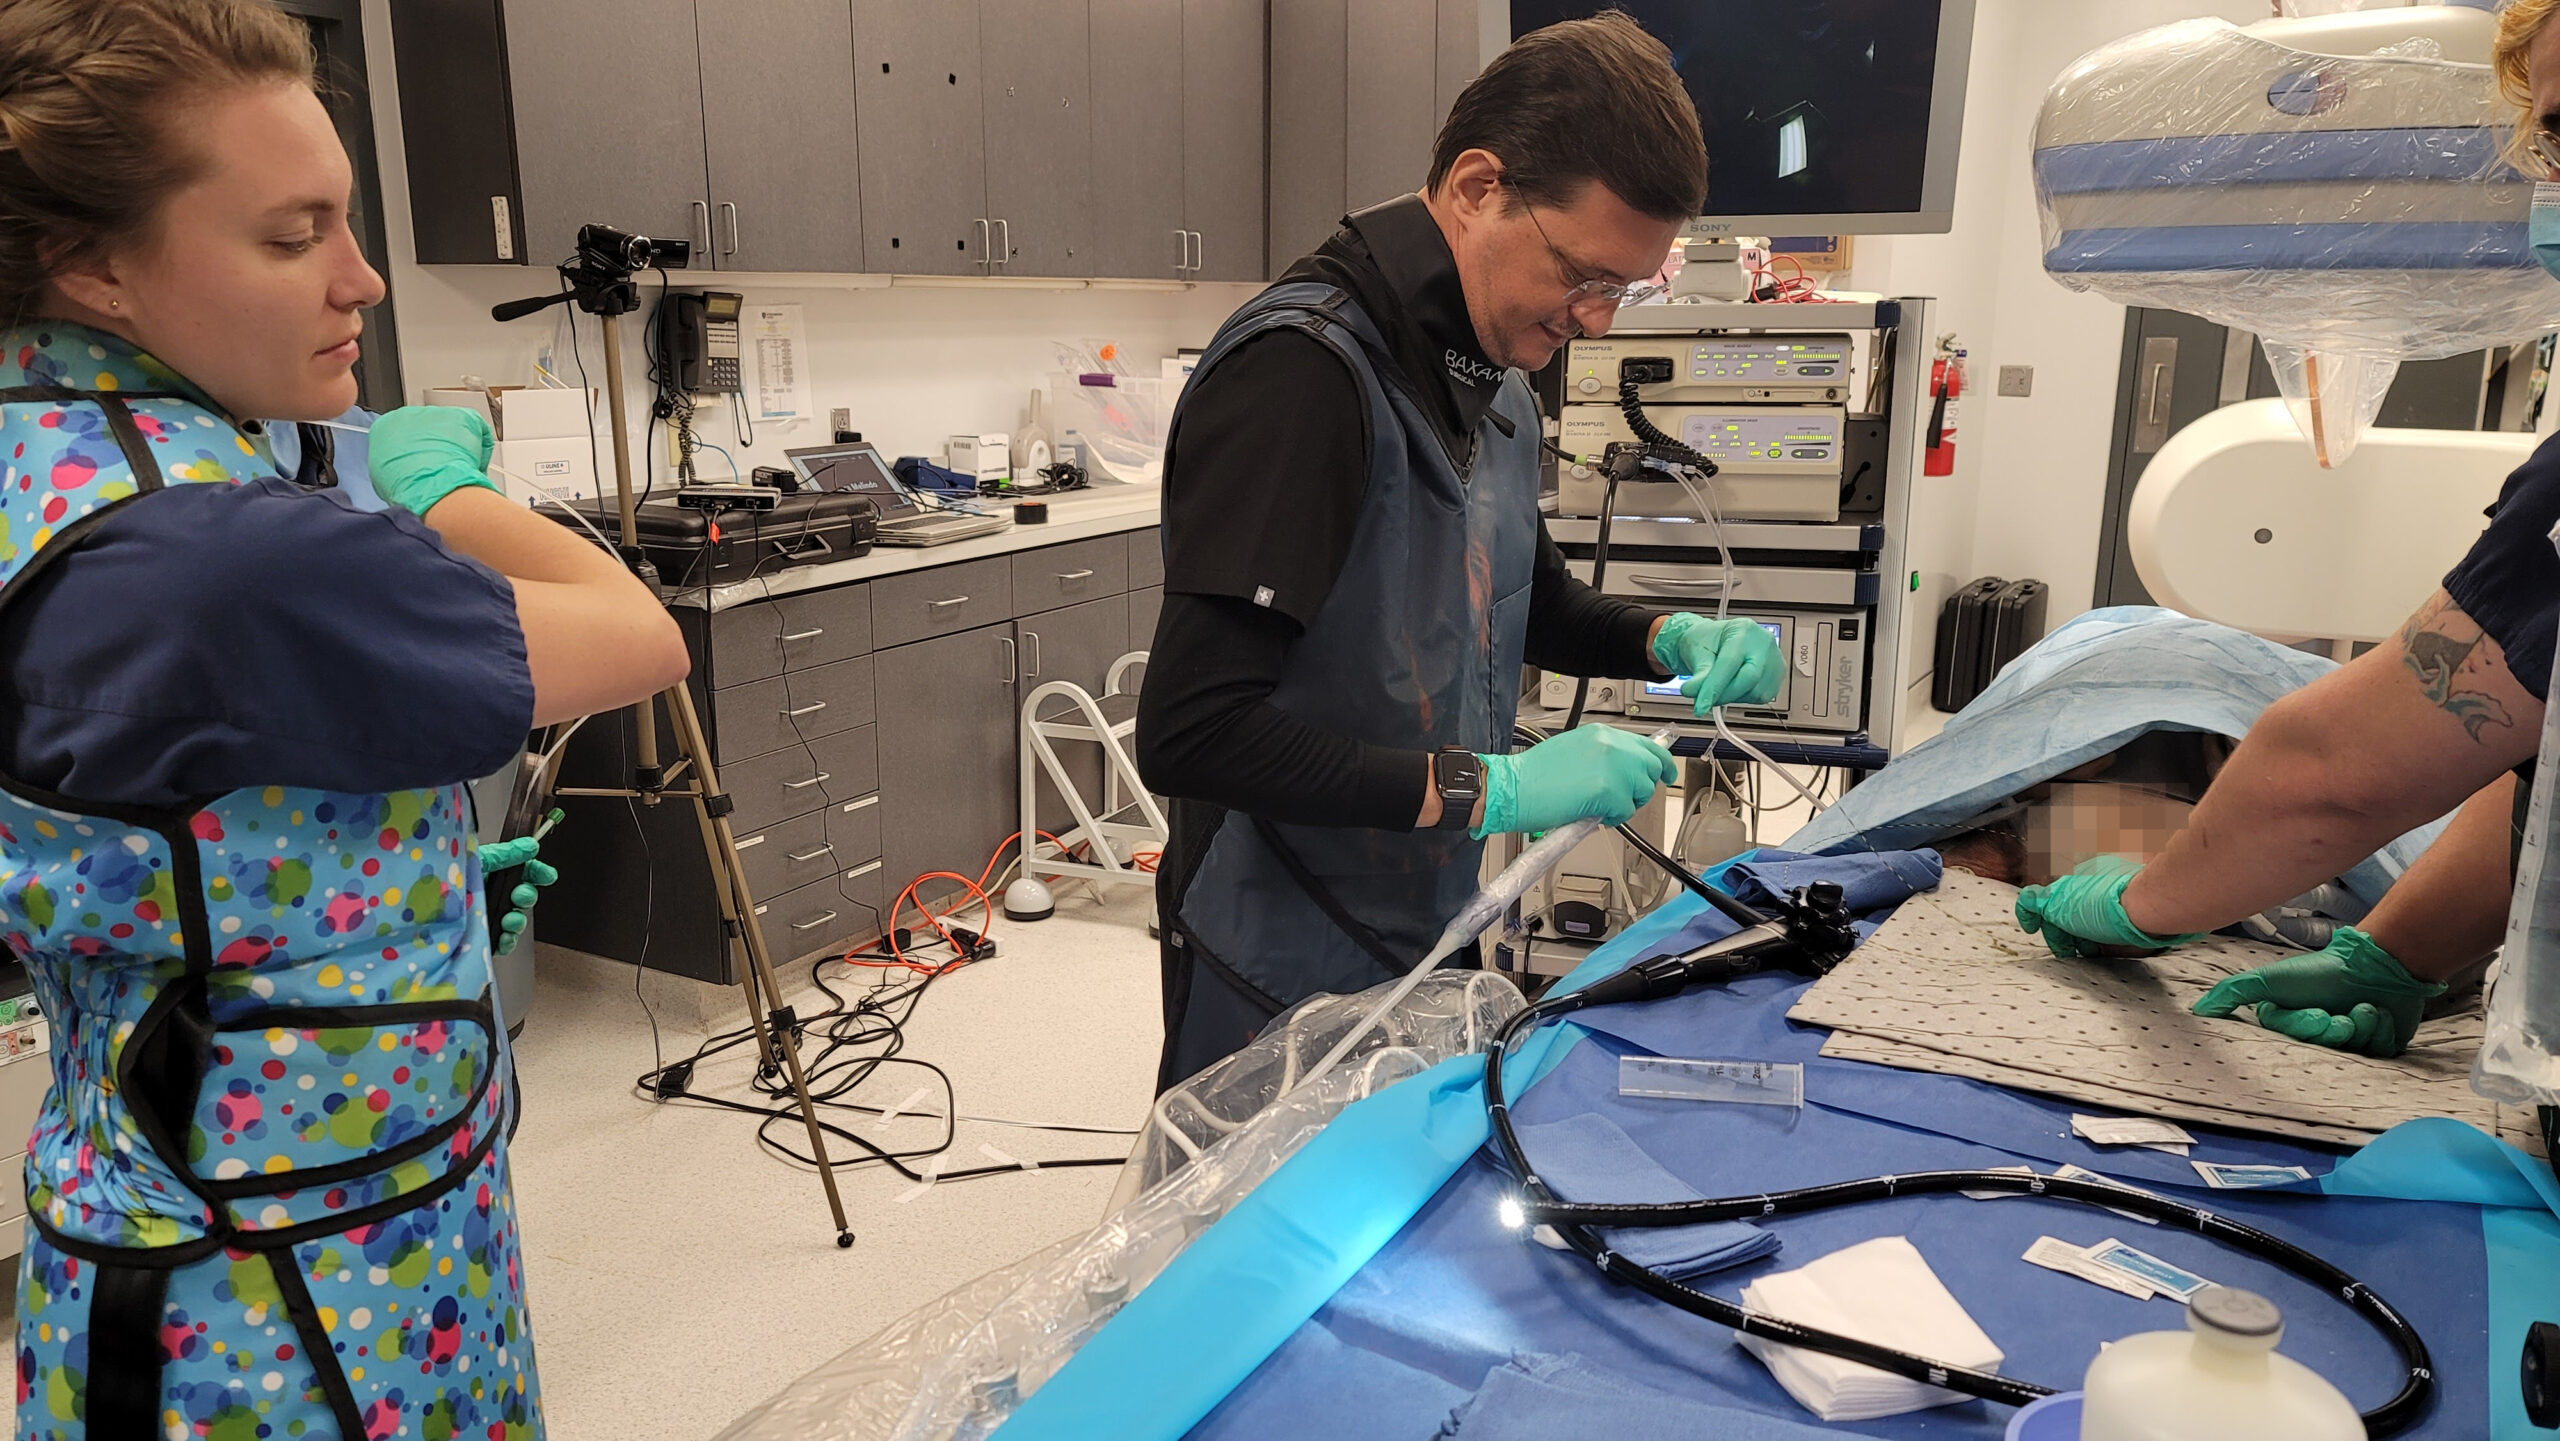

A fully incisionless procedure

The first cut-free endoscopic treatment for diabesity, ForePass ® is able to replicate the most common types of metabolic surgery (Roux-en-Y Gastric Bypass, RYGB, BilioPancreatic Diversion, and Sleeve Gastrectomy). The first version of our product is aimed at RYGB.

Designed to replicate metabolic surgery without any cuts to internal organs. As effective on diabetes and obesity as metabolic surgery in animals.